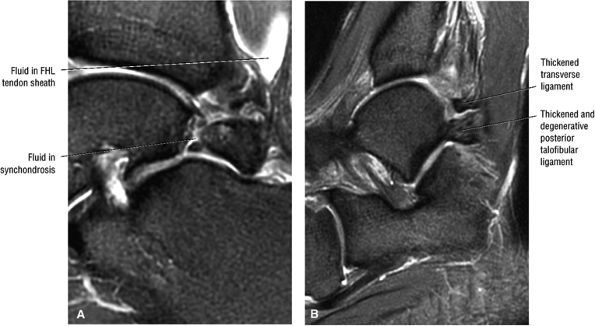

FIGURE 5.25 ● Sagittal anatomy of the ankle and foot. (A) The origins of the anterior talofibular ligament and posterior talofibular ligament are identified arising from the anterior and posterior distal tip of the lateral malleolus. From the origin, the full course of these ligaments can be followed medially on successive sagittal images to their insertions on the anterior and posterior talus. (B) The vertical course of a long segment of the peroneus longus and brevis tendons is often visualized on a single sagittal image through the tendons. This image is useful to further characterize tendinosis and longitudinal tears or splits, and for measuring the gap between completely ruptured tendon fragments. (C) The anterior process of the calcaneus is a common location for fractures that are occult on plain film. They are optimally visualized in the sagittal plane on MR exams. (D) In addition to occurring at the tibiotalar joint, degenerative arthrosis is also commonly found at the posterior subtalar, calcaneocuboid, and talonavicular joints. The cartilage surfaces and subchondral bone at these articulations are optimally visualized in the sagittal plane. (E) The presence of an os trigonum posterior to the talus predisposes certain athletes with a predilection for plantarflexion to the os trigonum syndrome. This is diagnosed on sagittal MR images when edema is visualized within the os trigonum and extends across the synchondrosis into the posterior talus. (F) Abnormal signal in the sinus tarsi manifests as high signal on FS fluid-weighted sequences and low signal on non-FS sequences. This abnormal signal may suggest, but is not specific for, inflammation in the sinus tarsi. Other causes of abnormal signal in the sinus tarsi, which may be incidental and asymptomatic, include extension of joint fluid from the posterior and middle subtalar joints, extension of generalized edema throughout the soft tissues of the ankle from stasis or other causes, enlarged vessels, and ganglion cysts.(G) Two potential causes of an incidental “mass” palpated on physical examination about the Achilles tendon are a low-lying soleus muscle and an accessory soleus muscle, both of which are diagnosed by MR imaging. The normal soleus muscle extends to about the proximal one third or one half of the Achilles tendon. A low-lying soleus will extend to the distal third of the tendon. An accessory soleus is present when there is an extra muscle in the pre-Achilles fat, usually extending to the distal third of the tendon, often near the distal insertion. (H) In the setting of a complete Achilles tendon rupture, the location of the tear may be at the myotendinous junction, mid-tendon, distal tendon, or tendon insertion at the os calcis. In addition, the tear is characterized as transverse or oblique longitudinal. In the case of transverse tears, the distance between the tear and tendinous insertion at the calcaneus is measured. Also, the length of good-quality tendon stump at the calcaneal insertion is measured, since the surgeon often uses the distal stump in the surgical reconstruction or repair. (I) The anteromedial aspect of the tibiotalar joint is a common location for the formation of large osteophytes, which extend anteriorly from the anteromedial tibia and talus. These may cause pain, limit the range of motion, or break off and form loose bodies within the tibiotalar joint. This spectrum of findings is part of the anteromedial impingement syndrome. (J) Ancillary findings at the plantar aponeurosis visualized on sagittal images include bone marrow edema within the inferior calcaneus, inferior calcaneal enthesophyte with marrow edema, and high signal within the flexor digitorum brevis muscle and fat that surround the plantar aponeurosis. These findings suggest active inflammation in the tissues surrounding the plantar aponeurosis. (K) The deltoid ligament is found on sagittal images by finding its origin extending off the bilobed medial malleolus. The medial course of the deltoid ligament components is followed over the next two or three successive sagittal images. (L) The vertical course of the tibialis posterior tendon and the flexor digitorum longus tendon is often visualized on a single image. Triangulating on tendon pathology in both the sagittal and axial planes aids in further characterizing tendon abnormalities.

FIGURE 5.27 ● Axial anatomy of the ankle and foot. (A) The flexor digitorum longus, flexor hallucis longus, peroneus brevis, soleus, and extensor digitorum muscles are examined at this level for strain, tears, or fatty atrophy that may suggest denervation. (B) The tibialis anterior, extensor hallucis longus, and extensor digitorum longus tendons are examined on every ankle MR examination. Extensor tendon pathology is frequently overlooked if these tendons are not included as part of the ankle checklist. (C) Tears and sprains of the anterior syndesmotic ligament are a frequent cause of persistent ankle pain following ankle sprain. The syndesmotic ligaments are thick, tough ligaments that are important ankle stabilizers, and delayed diagnosis of syndesmotic tears may result in significant degenerative arthrosis at the tibiotalar joint due to the resulting ankle instability. The syndesmotic ligaments course obliquely inferiorly from the tibia to the fibula and are not usually visualized in their entirety on a single axial image; rather, their course is followed on at least two or three successive axial images. (D) The peripheral margin of the peroneal tendons and tibialis posterior tendon should normally never extend beyond the peripheral margins of the lateral and medial malleoli, respectively. Tendon subluxation around the posterior corner of either malleolus is indicative of a tear of the overlying flexor retinaculum (medially) or peroneal retinaculum (laterally). When the retinacula are torn, the tendon is free to intermittently sublux or dislocate, leading to tendon degeneration, pain, and tendon dysfunction. (E) Suspected osteochondral lesions of the talar dome are visualized and further characterized on axial images through the top of the talar dome. (F) The peroneus brevis tendon may normally appear somewhat flattened. However, as the tendon degenerates, it becomes U-shaped and drapes around the anterior aspect of the peroneus longus and becomes impinged between the peroneus longus tendon and the lateral malleolus. With further degeneration, the peroneus brevis may split or completely rupture. (G) Evidence of anterior talofibular ligament injury is visualized on the majority of MR ankle examinations and appears as thickening, intermediate signal with ill-defined fibers, or attenuation of the ligament. This is commonly asymptomatic. (H) Because the flexor hallucis longus tendon sheath communicates with the tibiotalar joint, fluid may normally be present within the tendon sheath in proportion to the amount of fluid in the tibiotalar joint. If there is fluid within the tendon sheath out of proportion to that seen in the tibiotalar joint, tenosynovitis is most likely present. The finding of flexor hallucis longus tenosynovitis should prompt a search for an os trigonum, as impingement of the flexor hallucis longus tendon between an os trigonum and the posterior tibial plafond is a common cause for FHL tenosynovitis. (I) The calcaneofibular ligament (CFL) passes anterior and medial to the peroneal tendons. On the image at which the CFL passes directly medial to the peroneus brevis tendon, the appearance of the peroneus brevis and the CFL side by side is occasionally mistaken for a split peroneus brevis tendon. (J) Dilated posterior tibial veins within the tarsal tunnel occasionally compresses the tibial nerve. In the setting of clinical suspicion for tarsal tunnel syndrome or if there is evidence of muscle denervation on MR images, the size of the posterior tibial veins should be described. (K) The spring ligament is identified at this axial image location, extending from the anteromedial calcaneus to the posteromedial navicular. Tears of the spring ligament may result in medial instability and hindfoot valgus. (L) The posterior tibialis tendon (PTT) may normally become thickened and fan-like as it passes posterior to its navicular insertion (prior to also inserting on the cuneiforms and the base of the second through fourth metatarsals). In the absence of other findings, the thickening of the PTT at this level should not be mistaken for focal tendinosis. (M) On inferior images through the ankle, Lisfranc's ligament is occasionally included in the FOV. Lisfranc's ligament extends from the medial cuneiform to the base of the second metatarsal. If Lisfranc's ligament is included in the FOV, the status of the ligament should be described, as undiagnosed Lisfranc ligament tears can lead to debilitating midfoot arthrosis. (N) As the medial and lateral tendons turn from their vertical course to a horizontal course along the plantar aspect of the foot, the tendons may demonstrate a magic-angle artifact, causing the tendons to appear gray on short-TE images, mimicking tendinosis. Correlation with images using longer TE values is advised in such situations.